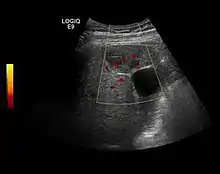

Dysplastic nodule (2D, CFM, CEUS). The nodule is well-defined with a size between 10– 20 mm, lacks vessels in CFM and CEUS exploration.

These lesions have various patterns (hypo or hyperechoic) with at least 1 cm diameter. They are hepatocytes with dysplastic changes, but without clear histological criteria for malignancy. They are divided into low-grade dysplastic nodules, where cellular atypia are mild and high-grade dysplastic nodules with moderate or severe cellular atypia, but without any established signs of malignancy. Occasionally, well-differentiated HCC foci can be identified in high-grade dysplastic nodules (appearance called "nodule in nodule") . Most authors accept the carcinogenesis process as a progressive transformation of DN from low-grade to high-grade and into HCC. The nodule's vasculature changes progressively, correlated with the degree of malignancy, and it is characterized by decrease until absence of portal venous input and by increase of arterial intratumoral input. Neoformation vessels occur with increasing degree of dysplasia. Arterial neovascularization is enhanced in a chaotic and explosive way, while normal, arterial and portal vasculature continues to decline. High-grade dysplastic nodules are hypovascularized both arterial and portal phases, while early HCC nodules may have similar arterial pattern with the surrounding parenchyma or exacerbated, and portal hypovascularization. In moderate or poorly differentiated HCC (classic HCC) tumor nutrition is performed only by neoformation vessels (abundant), the normal arterial and portal vasculature completely disappearing. This behavior of intratumoral vascularization is typical for HCC and is the key to imaging diagnosis.

B-mode ultrasonography is unable to distinguish between regenerative nodules and borderline lesions such as dysplastic nodules and even early HCC. Doppler examination also has a low sensitivity in differentiating dysplastic nodules from early HCC. Doppler signal may be absent in both regenerative and dysplastic nodules. Some authors indicate the presence of venous type Doppler flow which reflects the portal venous nutrition of the nodule as a characteristic feature of dysplastic nodules and early HCC (Minami & Kudo, 2010). Other authors noticed the presence of an arterial flow with small frequency variations and a normal resistivity index. On CEUS examination both RN and DN may have quite a variable enhancement pattern. Generally, both nodules enhances identically with the surrounding liver parenchyma after UCAs injection. Dysplastic nodules are hypovascular in the arterial phase. In case of highgrade dysplastic nodule sometimes a hypervascularization can be detected, but without associating "wash out" during portal and late CEUS phases. In these cases, biopsy may clarify the diagnosis.